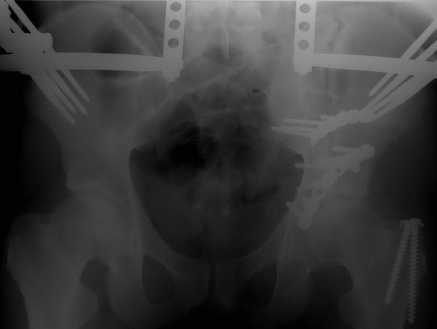

Добрый вечер, уважаемые коллеги. Прошу прощение за долгое молчание( компьютер был в долгосрочном ремонте). Больного с 9-ти месячной травмой таза мы прооперировали. Оценив свои возможности и совместив с вашими рекомендациями и советами (большое спасибо Рункову!), пошли задне-наружным доступом, с отсечением большого вертела. Закрепились 2-мя пластинками. Сверху закрепили аппаратом( передней рамой). На область перелома самого гребня повздошной кости не вмешивались. Снимки высылаю. Жду ваших отзывов и комментариев. Всем большое спасибо за активное участие в лечении больного. С ув.Андрей

Внутренняя фиксация получилась достаточно стабильная.А передняя рама наложена с целью дополнительной фиксации для нейтрализации мышц прикрепляющихся к крылу подвздошной кости, и исключить возможное расшатывание и возникнование нестабильности внутрених фиксаторов( уж очень большая нагрузка на эти 2 пластины).На открытом этапе операции мобилизовали только часть линии всего перелома( около 1/4 части начиная от свода и проксимально), а остальная часть находится в рубце и патологическая подвижность в ней есть хоть и не выражена) А о ранней нагрузке никто и не думал. А как на ваш взгляд, в какие сроки в такой ситуации разрешить полную нагрузку? Я считаю, что только при сращении перелома, подвержденные лучше бы КТ